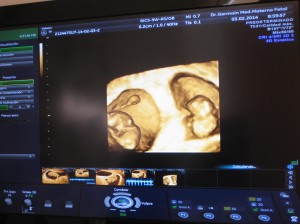

Hoy, Febrero de 2014, al final de mis 44 años y después de 10 años de matrimonio, ¡estoy entrando a la décima semana de embarazo de mellizos! Me he sentido un poco mal, pero ellos están perfectos!!!!!

Por Simone Henrique P. - 10 semanas de embarazo